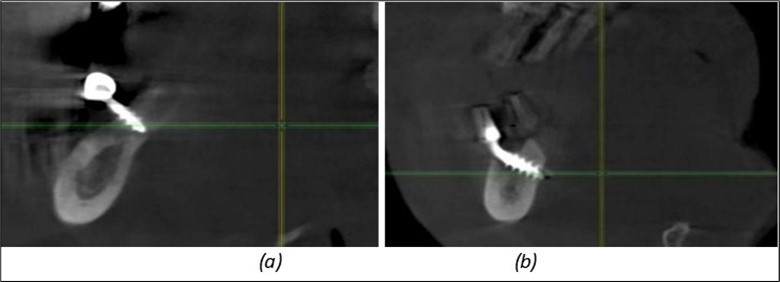

A total of 11 implants is placed in the maxilla, including compressive TPG implants with a polished surface in the maxillary-sphenoid fusion area (Figure 3, Figure 9). Similarly, in the anterior region, final fixation is achieved in the nasal cortex, and BCS corticobasal implants are added in areas with massive bone loss in the frontal region (Figure 3, Figure 8, Figure 11). Additionally, in the palatal sinus cortical area, with the aim of avoiding the addition and sinus lift zone where the second cortical bone no longer exists, 3 implants are placed, 2 in quadrant 1 and 1 in quadrant 2 (Figure 3, Figure 8). Through the Caldwell-Luc sinus lift procedure, the sinus cortical bone is displaced to allow the placement of the graft material and elevation of the sinus membrane. This sinus cortical is no longer recreated at the junction of the graft material and mucosa-sinus membrane, making it impossible to place a corticobasal implant, which relies on the second cortical bone. In the distal mandibular area, after the removal of two stage implants due to massive destruction in quadrant 3, implant placement distal to the mylohyoid line is not possible, as in quadrant 4 (Figure 10). A re-intervention occurs after 5 months to stabilize the area (Figure 12, Figure 14). Also, at the moment of fixation, the tip of one implant fractures, and the decision is made to leave it in place due to regional bone destruction, in order to avoid enlarging the bone defect.

In the interforaminal area (Figure 3, Figure 13), 6 corticobasal implants are also placed. The increased number of implants is due to the poorly represented distal area that needs to be compensated.

Figure 12.Implants fixed distally in quadrant 4 with fixation at the level of the mylohyoid line: (a) The most distal implant fixed in unaffected bone from the previous restoration; (b) The implant fixed in the area where the two stage implant was removed.

Figure 13.Corticobasal BCS implants fixed between the vestibular and lingual cortices with support on the basal bone: (a) BCS fixed between the lateral cortices; (b) BCS implant with support on the basal cortex.